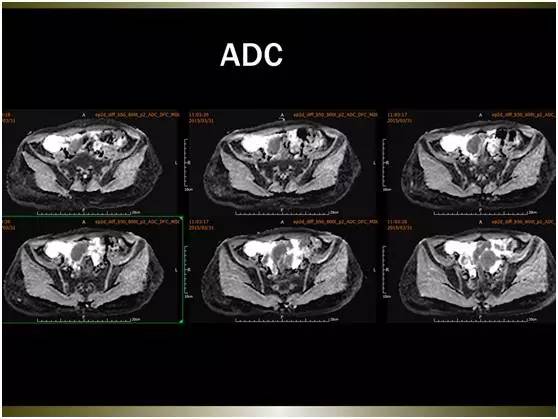

MR平扫及增强示:

大网膜、脏壁腹膜可见弥漫性大小不等略长T1略长T2异常信号,边界不清,FS-T2WI呈高信号,FS-T1WI呈略低信号。注入GD-DTPA后病变明显强化。